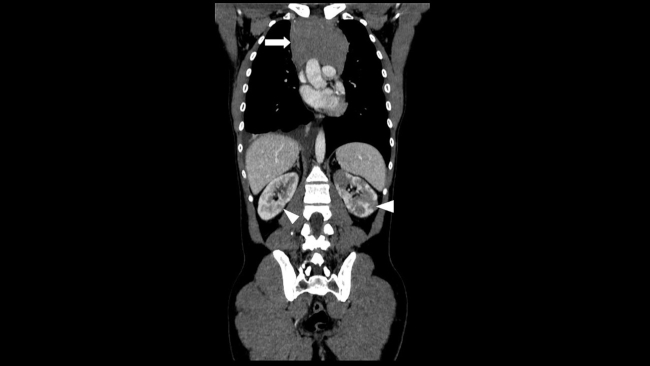

Presentamos el caso de un varón de 30 años que acudió al Servicio de Urgencias de nuestro hospital derivado por su médico de atención primaria, por la presencia de bultomas tumefactos y dolorosos a la palpación, localizados en el cuero cabelludo de un mes de evolución, predominando en zona parietal, temporal y occipital. Asociaba cefalea de características inespecíficas y astenia. Desde hacía dos semanas presentaba nódulos cervicales que impresionaban adenopatías preauriculares, retroauriculares y submandibulares. No presentaba fiebre ni sudoración nocturna. Refería pérdida de 1 a 2 kg en el último mes. Había sido tratado con minociclina 100 mg durante un mes sin mejoría. Durante su estancia, se realizó interconsulta con el Servicio de Dermatología, que completó el estudio con serologías de sífilis, virus de la inmunodeficiencia humana (VIH), hepatitis y citomegalovirus; biopsia de las lesiones de cuero cabelludo, cuyo resultado reveló linfoma / leucemia linfoblástica T; y se practicó punción aspirativa con aguja fina (PAAF) de adenopatía cervical, que confirmó el cuadro linfoide monomorfo. También se solicitó TC toracoabdominopélvica con contraste intravenoso (CIV) que puso de manifiesto: una masa mediastínica anterior que englobaba vasos con leve compresión y desplazamiento sugestiva de conglomerado adenopático y múltiples lesiones focales renales, bilaterales, así como engrosamiento apendicular sugestivos de infiltración linfomatosa (►Figs.1,2a,2b,3a,3b).

Existe una amplia variedad de manifestaciones radiológicas.1,3 La presencia de múltiples lesiones corticales nodulares es la forma más común, como en nuestro caso. Suelen ser bilaterales, de tamaño variable, típicamente de 1 a 4,5 cm de diámetro. Ante dicho hallazgo y los múltiples diagnósticos diferenciales que plantea (metástasis, carcinoma de células renales, pielonefritis, carcinoma de células transicionales, etc.) conviene completar el estudio con biopsia, si es el único hallazgo linfomatoso.2,3 En la TC sin CIV, aparecen como lesiones con una atenuación ligeramente más alta que la del parénquima circundante. La TC con CIV en fase nefrográfica es esencial porque muchas lesiones son pequeñas y afectan a la porción medular de los riñones, con mínima deformidad cortical. Los depósitos linfomatosos realzan menos que el tejido renal normal y aparecen como masas relativamente homogéneas e hipodensas.1,2

Por otro lado, existe la extensión retroperitoneal contigua, que es el segundo patrón más común. Se observan grandes masas retroperitoneales que invaden o desplazan el riñón adyacente.1,3 Generalmente, las arterias y venas renales permanecen permeables. Sin embargo, la extensión al sistema colector renal puede causar obstrucción e hidronefrosis.2